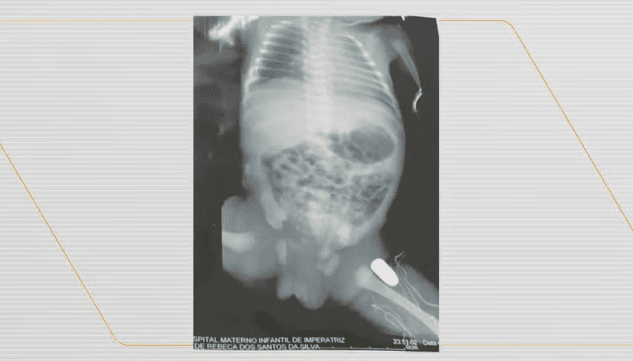

Uma grávida de 16 anos passou por uma cesárea de urgência após ser baleada durante um assalto, neste domingo (16/06), em Imperatriz, no Maranhão. A bala ficou alojada na perna do bebê.

A adolescente estava com o namorado quando foram surpreendidos por criminosos durante um assalto. O casal foi baleado e socorrido para uma unidade de saúde. O bebê vai ser operado ainda nesta segunda-feira (17/06) para retirar a bala.